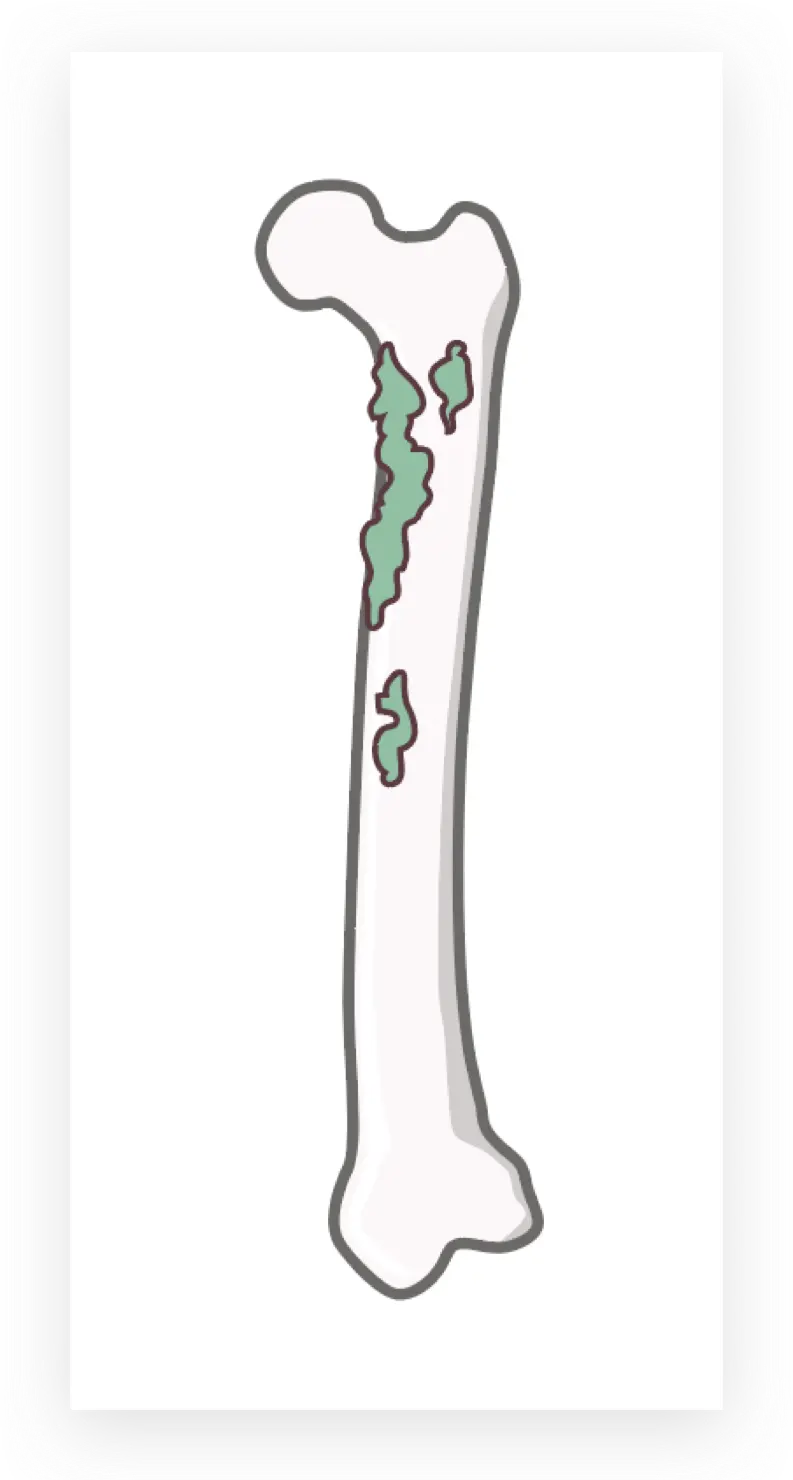

最后是骨头

先用钢笔工具勾勒出外轮廓

再上色

一层层叠加图层至完成